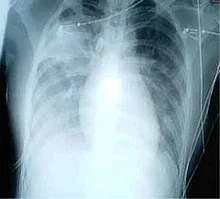

Οι περισσότεροι κορονοϊοί προκαλούν στον άνθρωπο συνήθως λοιμώξεις του ανώτερου αναπνευστικού, αλλά μπορούν να προκαλέσουν και πνευμονία. Είναι η αιτία του 10-15% των λοιμώξεων του αναπνευστικού συστήματος. Ένας κορονοϊός ήταν υπεύθυνος για μια έξαρση κρουσμάτων σοβαρού οξέως αναπνευστικού συνδρόμου (ΣΟΑΣ, διεθνώς γνωστό ως SARS), η οποία άρχισε το 2002 στην Κίνα.[1] Ένα άλλο είδος κορονοϊού προκάλεσε το αναπνευστικό σύνδρομο της Μέσης Ανατολής το 2012 (MERS). Μέχρι το 2019 είχαν καταγραφεί 2.468 κρούσματα με 851 θανάτους (θνητότητα περίπου 34,5%).[3] Στα τέλη του 2019, εμφανίστηκε ένας νέος κορονοϊός, o κορονοϊός της Ουχάν (γνωστός επίσημα ως SARS-CoV-2), ο οποίος προκάλεσε πανδημία. Οι κορονοϊοί έχουν σχετιστεί επίσης με γαστρεντερίτιδα.[1]